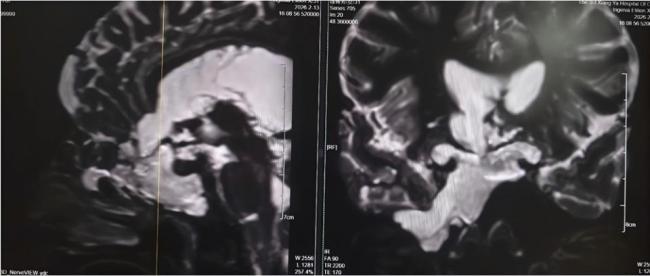

入院后,湘雅三医院功能神经外科杨靓副主任医师团队迅速为刘女士进行了全面检查。经系统评估与综合分析,专家团队明确诊断刘女士所患疾病为与脑室相通的高流量脑脊液漏,且颅内感染情况较为严重。此类高流量脑脊液漏病情复杂,治疗难度极高。若直接进行修补手术,术后极易因颅内压力过高导致修补失败;若在感染未充分控制前贸然封堵漏口,可能因失去引流通道导致颅内压骤升,进而造成病情急剧恶化,甚至危及患者生命。

为确保治疗安全有效,杨靓主任团队为刘女士制定了阶梯式治疗方案:先通过脑室—腹壁外引流术控制感染,再进行精准修补漏口。2月14日,杨靓主任团队为刘女士实施了脑室—腹壁外引流术,通过手术将其颅内感染的脑脊液引流至体外,同时联合规范的抗生素治疗,双管齐下控制感染。经过持续引流和脑脊液更新,刘女士的感染症状迅速得到控制,体温逐渐恢复正常,意识也逐步清醒,病情趋于平稳。